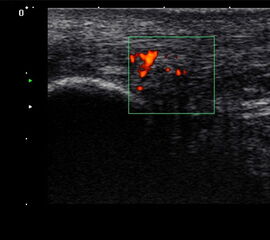

Die Farb-Doppler-Sonographie wurde 2001 erstmalig von Ohberg und Alfredson in Umea in Schweden bei schmerzhaften Achillessehnen eingesetzt 17. Bei 21 symptomatischen Sehnen konnten intratendionös mit Hilfe der Farb-Doppler-Sonographie pathologische Blutgefäße als Neovaskularisation nachgewiesen werden, die sich bei Achilles-gesunden Kontrollgruppe nicht fanden. Wenig später berichtete dieselbe Arbeitsgruppe über die erfolgreiche Farb-Doppler-kontrollierte Sklerosierung der Neogefäße mit Polidocanol 18.

2001 verglich Richards et al. die Power-Doppler-Sonographie bei symptomatischen Achillessehnenbeschwerden mit der Magnetresonanztomographie 19. Die Neogefäße in der Power-Doppler-Sonographie korrelierten mit Signalveränderungen in den T2-gewichteten MRT-Sequenzen. Aufgrund der guten Reproduzierbarkeit und Verfügbarkeit hat sich die Power-Doppler-Sonographie inzwischen bei der Darstellung der kleinen Neogefäße mit ihrem langsamen Blutfluss etabliert 202122. Die Neogefäße dringen von ventral in die Achillessehne ein. Typischerweise sind diese Neogefäße erst ab einem Sehnendurchmesser von >6,5mm nachweisbar. Bei erfolgreich behandelter Achillestendinopathie kann nach einem Jahr ein Rückgang der Anzahl der Neogefäße in der Power-Doppler-Sonographie, eine Durchmesserreduktion sowie eine Normalisierung der MRT-Signalalteration beobachtet werden 23. In einer Fallstudie konnte ein Abfall des Neovaskularisationsvolumens bei einem Patienten mit mid-portion Achillestendinopathie von 463mm3 auf 117mm3 belegt werden 24. Dies ging mit einer Verbesserung des Schmerzes in der visuellen Analogskala (von 8 auf 0) und des VISA-Scores (von 2 auf 92) einher.

634 asymptomatische Marathonläufer wurden mit der hochauflösenden Power-Doppler-Sonographie (12MHz) anlässlich von 23 Marathonveranstaltungen und 6 und 12 Monate im Anschluss untersucht 25. Mit einer odds ratio von 6.9 (p<0,001) konnte eine Neovaskularisation bei asymptomatischen Läufern die Entwicklung einer midportion Achillestendinopathie anzeigen. Eine positive Vorgeschichte für Achillessehnenbeschwerden hatte eine odds ratio von 3,8 und stellt damit ebenfalls einen ernst zu nehmenden Risikofaktor für weitere Beschwerden dar.